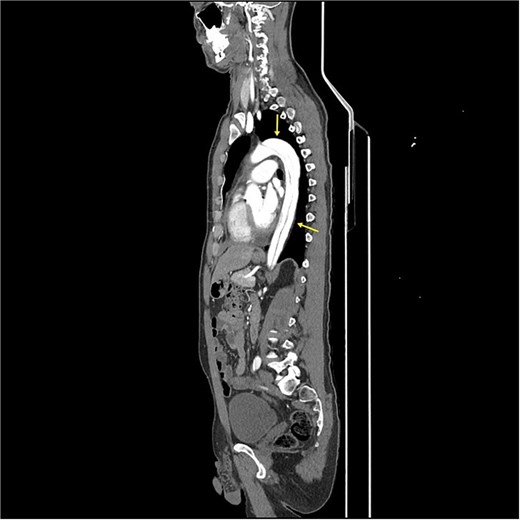

CT angiography revealed a Type A aortic dissection, stretching from the aortic valve to the femoral arteries, with cessation of blood flow halfway down the femoral artery and distally (Figs 1 and 2). An acute echocardiogram showed a dilated aortic sinus (42 mm) and ascending aorta (53 mm), with moderate aortic insufficiency. During these investigations, the patient was stable, awake, and without pain. Thrombolytic treatment was stopped immediately, and systolic blood pressure was kept <110 mmHg by labetalol and nitroglycerin.

CT-scan pre-operatively showing Type A aortic dissection from the ascending aorta to the femoral arteries.